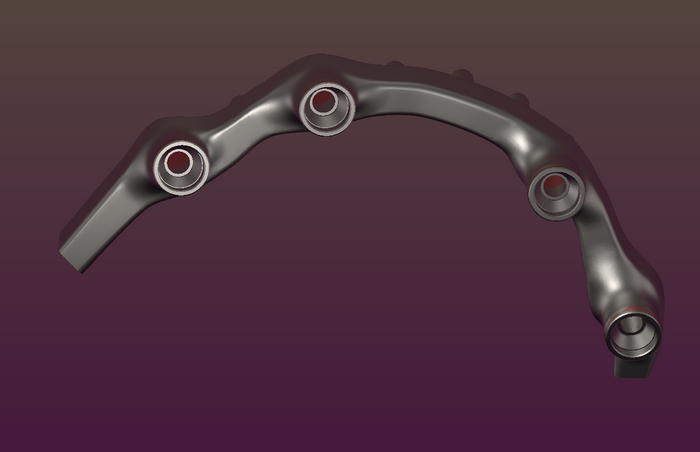

Следующий этап нанесения опакового (непрозрачного) слоя. Он выполняет двойную функцию: маскирует серость титана и является связкой металл–акрил.

верхний протез – временный, по этому у него изначально смоделирована десна. Нижний – постоянный. На него буду наносить фотополимерный композит, схожий или такой-же как и пломбировочный материал.